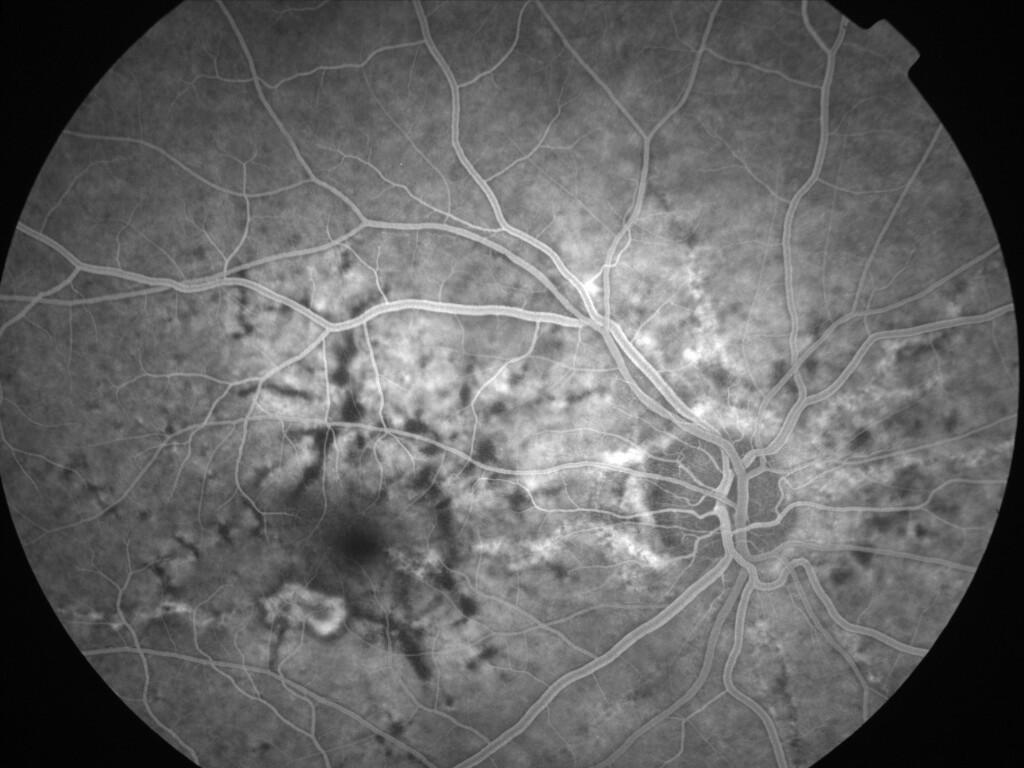

ASSOCIATION STRIES ANGIOIDES ET DYSROPHIE MACULAIRE RETICULEE

NEOVASCULARISATION